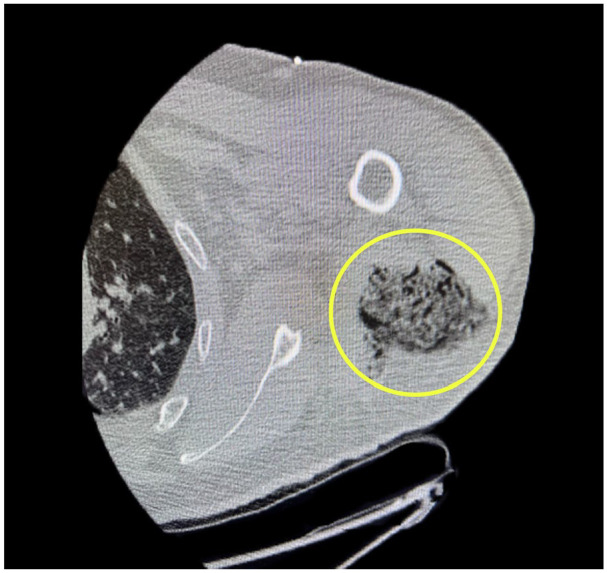

Nontraumatic clostridial myonecrosis infections are predominantly caused by Clostridium septicum. Most patients have an underlying gastrointestinal malignancy. This case presents a rare association of spontaneous clostridial myonecrosis preceding cerebral septic emboli with underlying invasive colorectal adenocarcinoma. A 60-year-old male with a history of hypertension, diabetes, and a family history of colon cancer presented to the emergency room with worsening left-sided chest pain radiating to his left shoulder. Extensive workup revealed elevated D-dimer, troponin, C-reactive protein, white blood cell count, and creatinine phosphokinase. Due to his clinical signs, symptoms, elevated white count, and further decompensation, he was started on antibiotics for sepsis. Physical exam revealed left upper extremity (LUE) crepitus consistent with imaging of innumerable soft tissue gas collections along the LUE. Incision, drainage, and myomectomy were performed due to concerns of myositis and necrotizing infection. Muscle biopsy revealed myonecrosis, and subsequent samples were positive for C. septicum. Postoperative pressor support and several sessions of surgical debridement were required. He continued to deteriorate and developed left-sided paralysis. Computed tomography head revealed several white matter infarcts indicative of septic emboli. The patient slowly recovered neurologically after switching to central nervous system-penetrating antibiotics. Months later, a colonoscopy revealed cecal adenocarcinoma. This case features a unique course of spontaneous C. septicum infection. There are high mortality rates, and previous studies report an association with colorectal malignancies. Therefore, preventative and diagnostic evaluations are imperative with a confirmed C. septicum infection. To our knowledge, this is the first case reported of cerebral septic emboli secondary to spontaneous myonecrosis with C. septicum, highlighting a unique burden of emboli-induced neurological deficits.